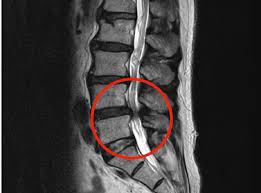

✅ 허리협착증이란?

허리협착증은 척추 속 신경이 지나가는 통로인 '척추관'이 좁아지면서, 신경을 눌러 통증이나 저림 등의 증상을 유발하는 질환입니다.

- 요추관협착증은 주로 허리 부분(L3~L5)의 협착으로 인해 발생합니다.